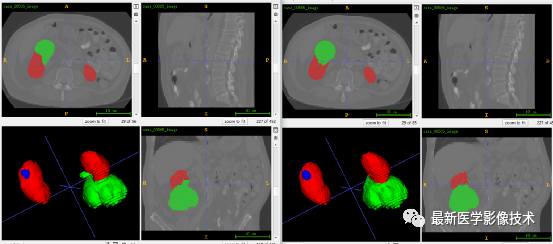

5、验证集分割结果

左图是金标准结果,右图是预测结果。